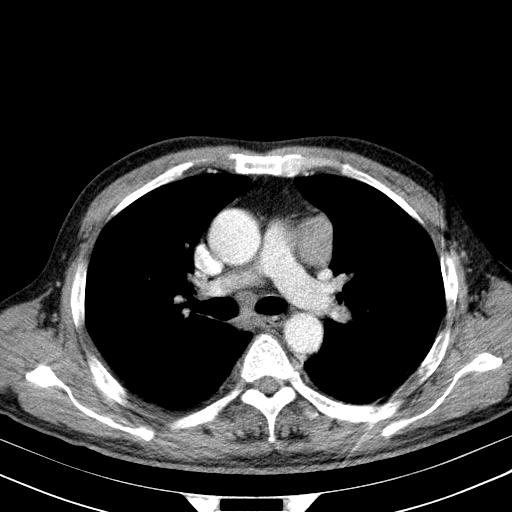

先行ct平扫,纵膈内多发软组织影,ct值约为36hu,以下为增强扫描和腹部平扫。

经典?纵膈多发肿大淋巴结。腹膜后未见异常。

1)考虑淋巴瘤。2)双侧少量胸腔积液。